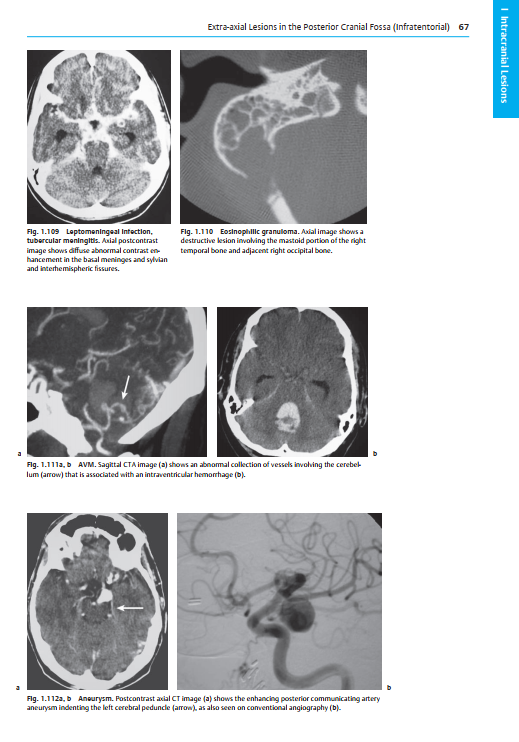

Continuation of the successful Burgener concept: Comprehensive tables describe the imaging patterns of the various diseases that may present on CT, along with other characteristically associated imaging findings and pertinent physiopathologic, pathologic, and clinical data

Over 2,000 detailed, high-quality images demonstrating a wide range of common and uncommon CT findings

Chapters organized according to anatomic regions, from the brain to the pelvis and the musculoskeletal system, with new chapters on meningeal and calvarian lesions and on trauma

Updated and revised sections reflecting the latest advances in CT technology and indications, including accurate staging of intra-articular and spinal fractures and evaluation of vascular diseases

Extensive index systematically cross-references diseases and CT findings for optimal access to information